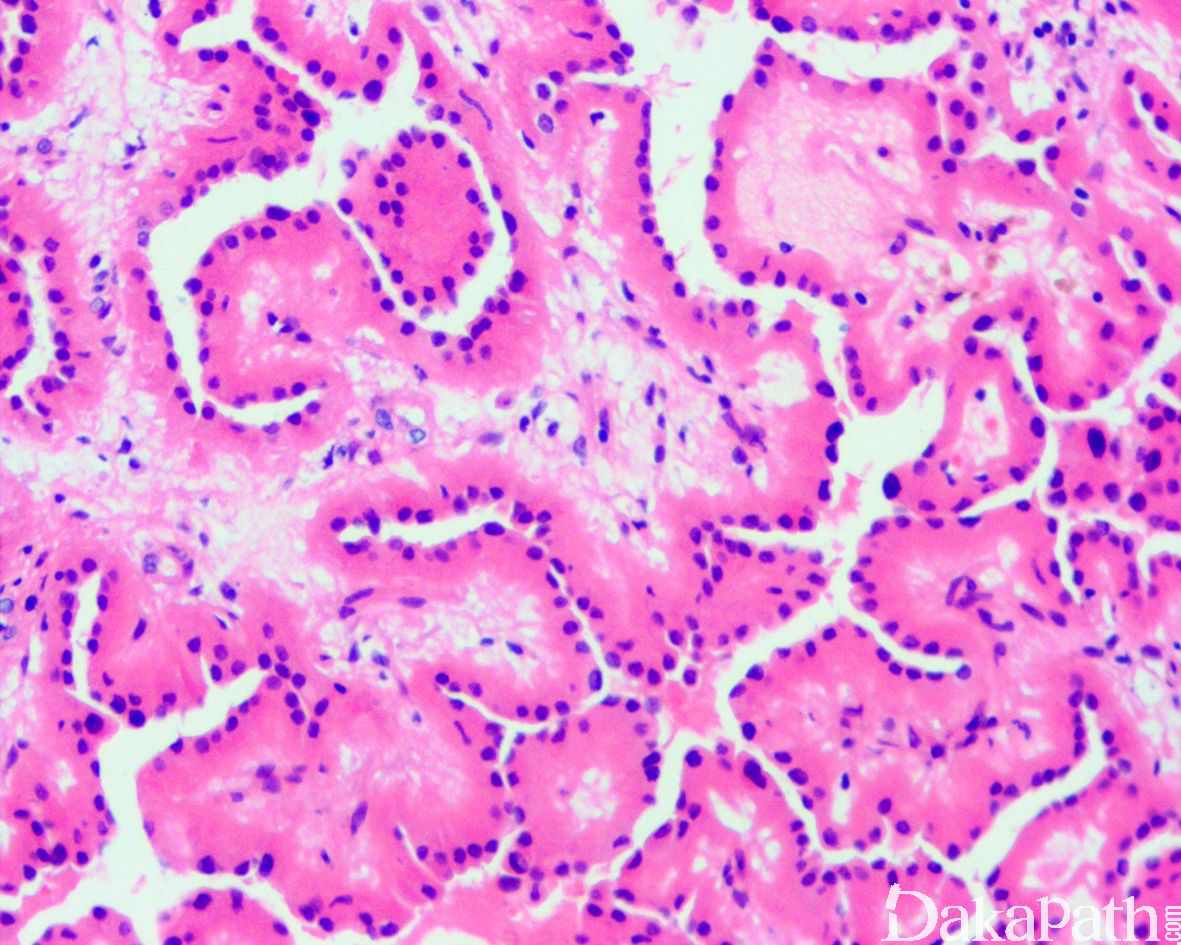

低倍镜下肿瘤主要由具有纤维血管轴心纤细的乳头状结构组成,伴有多少不等的管状结构;偶尔可见较厚的乳头或纤维血管轴心伴有玻璃样变性,以及囊性扩张的乳头;

乳头被覆单层立方状肿瘤细胞,具有丰富的嗜酸性颗粒状胞浆,部分可见胞浆内空泡,肿瘤细胞具有特征性的核,核位于远离基底膜的瘤细胞的胞浆顶端,乳头或小管腔面平滑;

核大小较一致,无重叠,轮廓规则,偶见核透明、核固缩或轻度不规则,核仁不明显(WHO/ISUP 核分级:1-2 级);

无砂粒体沉积、细胞内含铁血黄素沉积、核分裂象、肿瘤性坏死以及呈簇的泡沫细胞聚集。